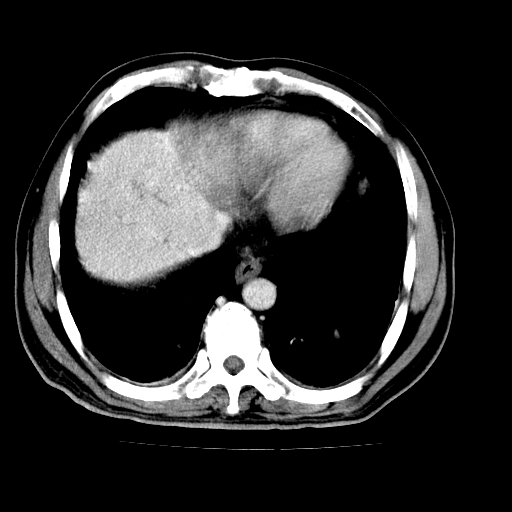

男,66岁,上腹部不适、黄染一周。彩超示:肝左叶占位,肝内胆管扩张,胆总管扩张,胆总管占位?

肝左叶不规则软组织肿块影,边缘不规整邻近肝实质受累分界不清;肝内胆管(左叶)明显扩张成“软藤状”,诊断:肝左叶胆管细胞癌。

支持肝左叶肝内胆管细胞癌伴胆总管及门脉左支受侵。

胆囊缩小,其内胆汁浓缩,也提示梗阻部位应该位于胆囊管起始部以上或是胆囊管受累及,支持肝外胆管癌。